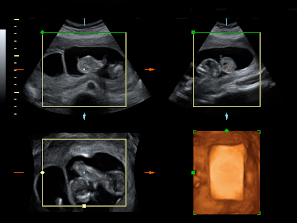

Los movimientos de estos gemelos de 12 semanas de gestación son extraordinariamente claros en la ecografía 4D. Los bebés mueven todo su cuerpo, especialmente brazos y piernas, adoptando multitud de posturas. Destaca el aspecto fieramente humano de los fetos, a pesar de su diminuto tamaño. Cuentan con dos placentas y dos bolsas independientes; la gruesa membrana de separación entre los bebés es visible en el registro ecográfico.

Ecografía 4D de gemelos de 12 semanas moviendo sus extremidades

Ecografía Embarazo 4D Semana 12 - ANOMALIAS CROMOSÓMICAS